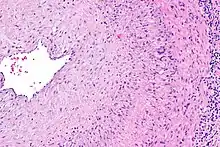

The gold standard for diagnosing temporal arteritis is biopsy, which involves removing a small part of the vessel under local anesthesia and examining it microscopically for giant cells infiltrating the tissue.[23] However, a negative result does not definitively rule out the diagnosis; since the blood vessels are involved in a patchy pattern, there may be unaffected areas on the vessel and the biopsy might have been taken from these parts. Unilateral biopsy of a 1.5–3 cm length is 85-90% sensitive (1 cm is the minimum).[24] Characterised as intimal hyperplasia and medial granulomatous inflammation with elastic lamina fragmentation with a CD 4+ predominant T cell infiltrate, currently biopsy is only considered confirmatory for the clinical diagnosis, or one of the diagnostic criteria.[11]

Mechanism

The pathological mechanism is the result of an inflammatory cascade that is triggered by an as of yet undetermined cause resulting in dendritic cells in the vessel wall recruiting T cells and macrophages to form granulomatous infiltrates.[19] These infiltrates erode the middle and inner layers of the arterial tunica media leading to conditions such as aneurysm and dissection.[19] Activation of T helper 17 (Th17) cells involved with interleukin (IL) 6, IL-17, IL-21 and IL-23 play a critical part; specifically, Th17 activation leads to further activation of Th17 through IL-6 in a continuous, cyclic fashion.[19] This pathway is suppressed with glucocorticoids,[20] and more recently it has been found that IL-6 inhibitors also play a suppressive role.[19]